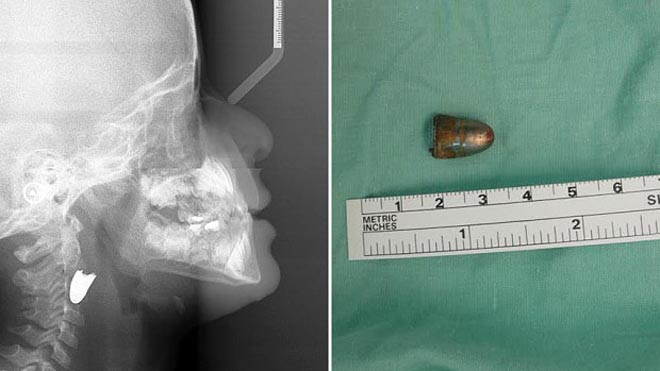

Bức ảnh chụp X-quang và hình ảnh viên đạn sau phẫu thuật (Ảnh: Telegraph)

Các bác sĩ cho biết họ mất vài giờ để phẫu thuật loại bỏ viên đạn găm trong cổ cậu bé. Đây là ca phẫu thuật khó khăn bởi viên đạn găm gần như trúng vào những mạch máu chính.

“Quả là một phép màu, cậu bé đã qua khỏi nguy kịch. Viên đạn đi theo một quỹ đạo kì lạ”, bác sĩ Karam nói.